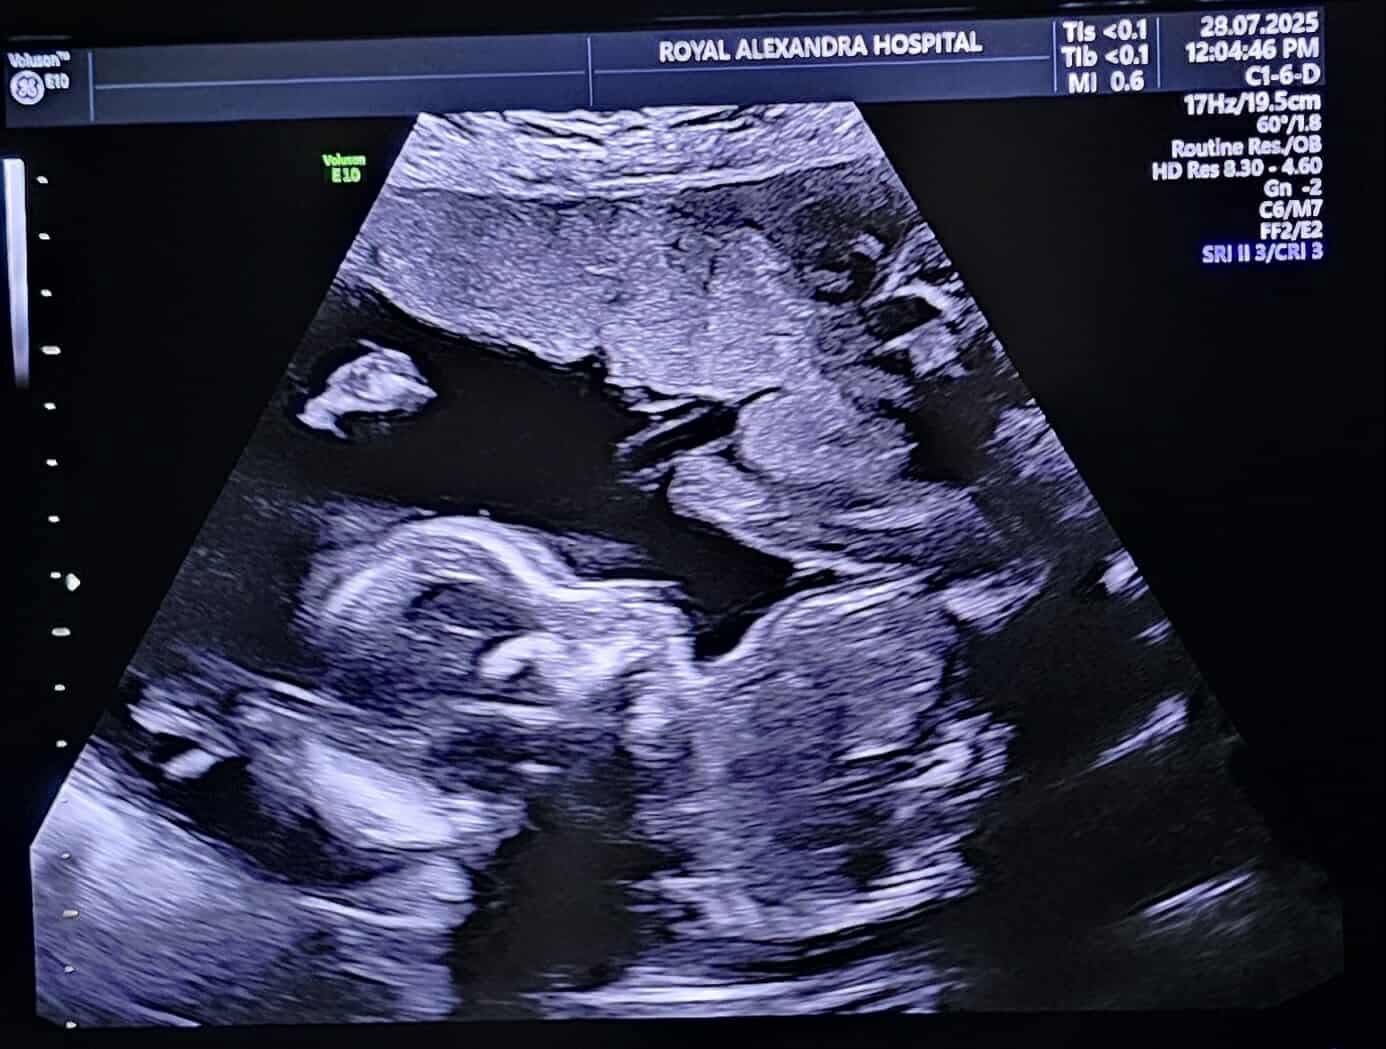

I'm reaching out on behalf of my cousin Haley, her husband Jordan, and their two young boys. Haley is currently 22 weeks pregnant with their third child, a baby girl, and this pregnancy has taken a sudden and difficult turn.

Recently, they learned that their baby has a rare and serious heart condition called a Complete Heart Block. This condition causes the baby's heart to beat dangerously slow and will require specialized care both before and after birth. She will need surgery to implant a pacemaker, likely shortly after birth. This will then be followed by lifelong cardiac monitoring, treatments, and surgeries.